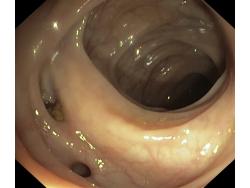

Uchyłki